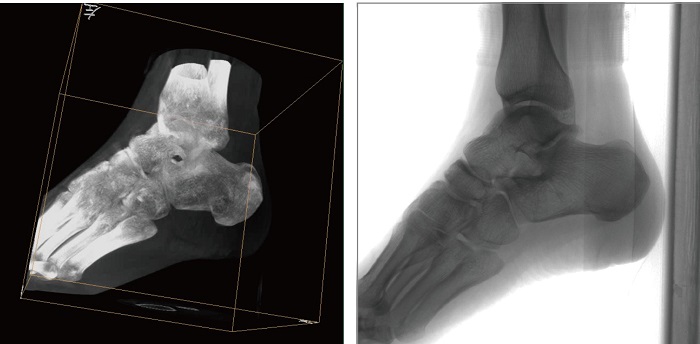

1、術(shù)中三維成像。PLX C7500A三維C型臂的術(shù)中三維成像和類CT切片圖像提供更全面的手術(shù)診斷信息,輔助醫(yī)生進行術(shù)中準確評估判斷諸如骨折復位情況和內(nèi)植入螺釘?shù)某叽绾臀恢?,保證了手術(shù)高精度地完成。

2、動態(tài)平板探測器。PLX C7500A三維平板C臂機采用30cmx30cm的動態(tài)平板探測器,輸出高分辨率、大尺寸的二維、三維圖像。達到16比特灰階度,高動態(tài)范圍清晰顯示植入物的位置和輪廓。

3、穩(wěn)定全面的圖形采集。PLX C7500A三維平板C形臂具有等中心掃描技術(shù),始終保持拍攝主體處于射線束的中心,避免C臂機架的橫縱方向的運動,從根源上減少了運動偽影了產(chǎn)生,提升圖像的清晰度。同時可190°三維采集角度,電驅(qū)動沿軌道滑轉(zhuǎn),提供高精度、全方位的三維圖像及類CT切片圖像信息。